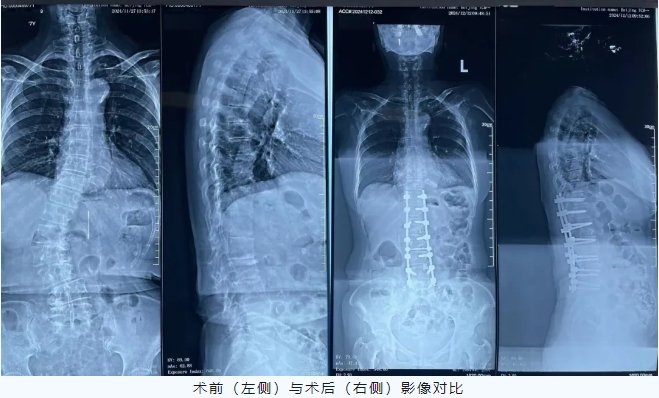

宽街·妙手 | 77岁老人“长高”4厘米,腰不痛、腿不软了……一场手术扶正侧弯脊柱,这种病老年人很常见

齐奶奶十几年前就开始出现腰痛,随着年龄的增长,腰痛慢慢加重、脊柱逐渐出现歪斜、双腿无力。近年来,病情愈发严重,连站立行走等日常生活都很难进行。齐奶奶和家人辗转北京多家大型三甲医院就诊,但却因年龄大、侧弯矫形手术创伤大等原因,医生均建议她保守治疗。难道晚年就要在轮椅上度过了?为了更高的生活质量,齐奶奶仍想为自己争取治疗机会。在家人推荐下,抱着满腔信任和一丝希望的她慕名来到了北京中医医院骨伤科韦竑宇主任医师门诊就诊。韦竑宇认真查看了既往的检查结果和齐奶奶的情况。一句“可以手术!”的答复仿佛一颗定心丸,驱散了齐奶奶和家属心头的阴霾。入院后,骨伤科医疗团队为齐奶奶进行了全面检查,在放射科支持下,进一步为齐奶奶完善脊柱全长片测量,脊柱侧弯Cobb角高达42°。由于成人侧弯脊柱僵硬,必须做到每个节段都进行减压松解才能实现矫形,创伤较大,不利高龄患者术后恢复。

为此,韦竑宇带领尹辛成、董春科、张翔、肖辉灯主诊团队术前完善了详细的手术方案,制定患者矫形节段(T11-L5)。由于齐奶奶年龄大且存在多种并发症,麻醉风险较高,麻醉科制定了详细的麻醉方案为手术保驾护航。术中医疗团队采用超声骨刀进行椎板切除减压,并且采用创伤更小的多节段TLIF截骨矫形术。在团队密切配合下,手术取得圆满成功。

术后在护理团队的精心呵护下,齐奶奶恢复良好,腰不痛了、脊柱变直了、个子“长高”了4cm,终于又可以抬头挺胸往前走了。